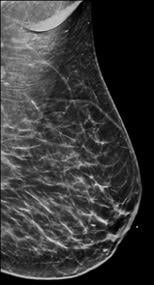

Breast density is divided into four categories, from lowest to highest amounts of fibroglandular tissue composition. Category A: Almost entirely fatty (least amount of fibroglandular tissue). Category B: Scattered fibroglandular tissue. Category C: Heterogeneously dense. Category D: Extremely dense (most amount of fibroglandular tissue).

Breast tissue is composed of a mixture of milk ducts, glands and supportive tissue, which is collectively called fibroglandular tissue and fat. The radiologist who reviews the mammogram analyzes overall breast density, which is the ratio of the amount of fibroglandular tissue to fatty tissue. Women with dense breasts have more fibroglandular tissue than fatty tissue. Fibroglandular tissue appears white on a mammogram and fat appears black. It becomes harder to detect a white cancer against a white background — imagine trying to find a polar bear in a blizzard. Dense tissue is harder to see through to detect abnormal findings. As breast density increases, cancer detection becomes more difficult. Additionally, breast cancer risk rises with increasing breast density. Multiple studies have indicated that there is a two- to six-fold increased risk of breast cancer for a woman who has an extremely dense breast versus a woman with an almost entirely fatty breast.4

Breast density is divided into four categories, from lowest to highest amounts of fibroglandular tissue composition:

Category A: Almost entirely fatty (least amount of fibroglandular tissue)

Category B: Scattered fibroglandular tissue

Category C: Heterogeneously dense

Category D: Extremely dense (most amount of fibroglandular tissue)